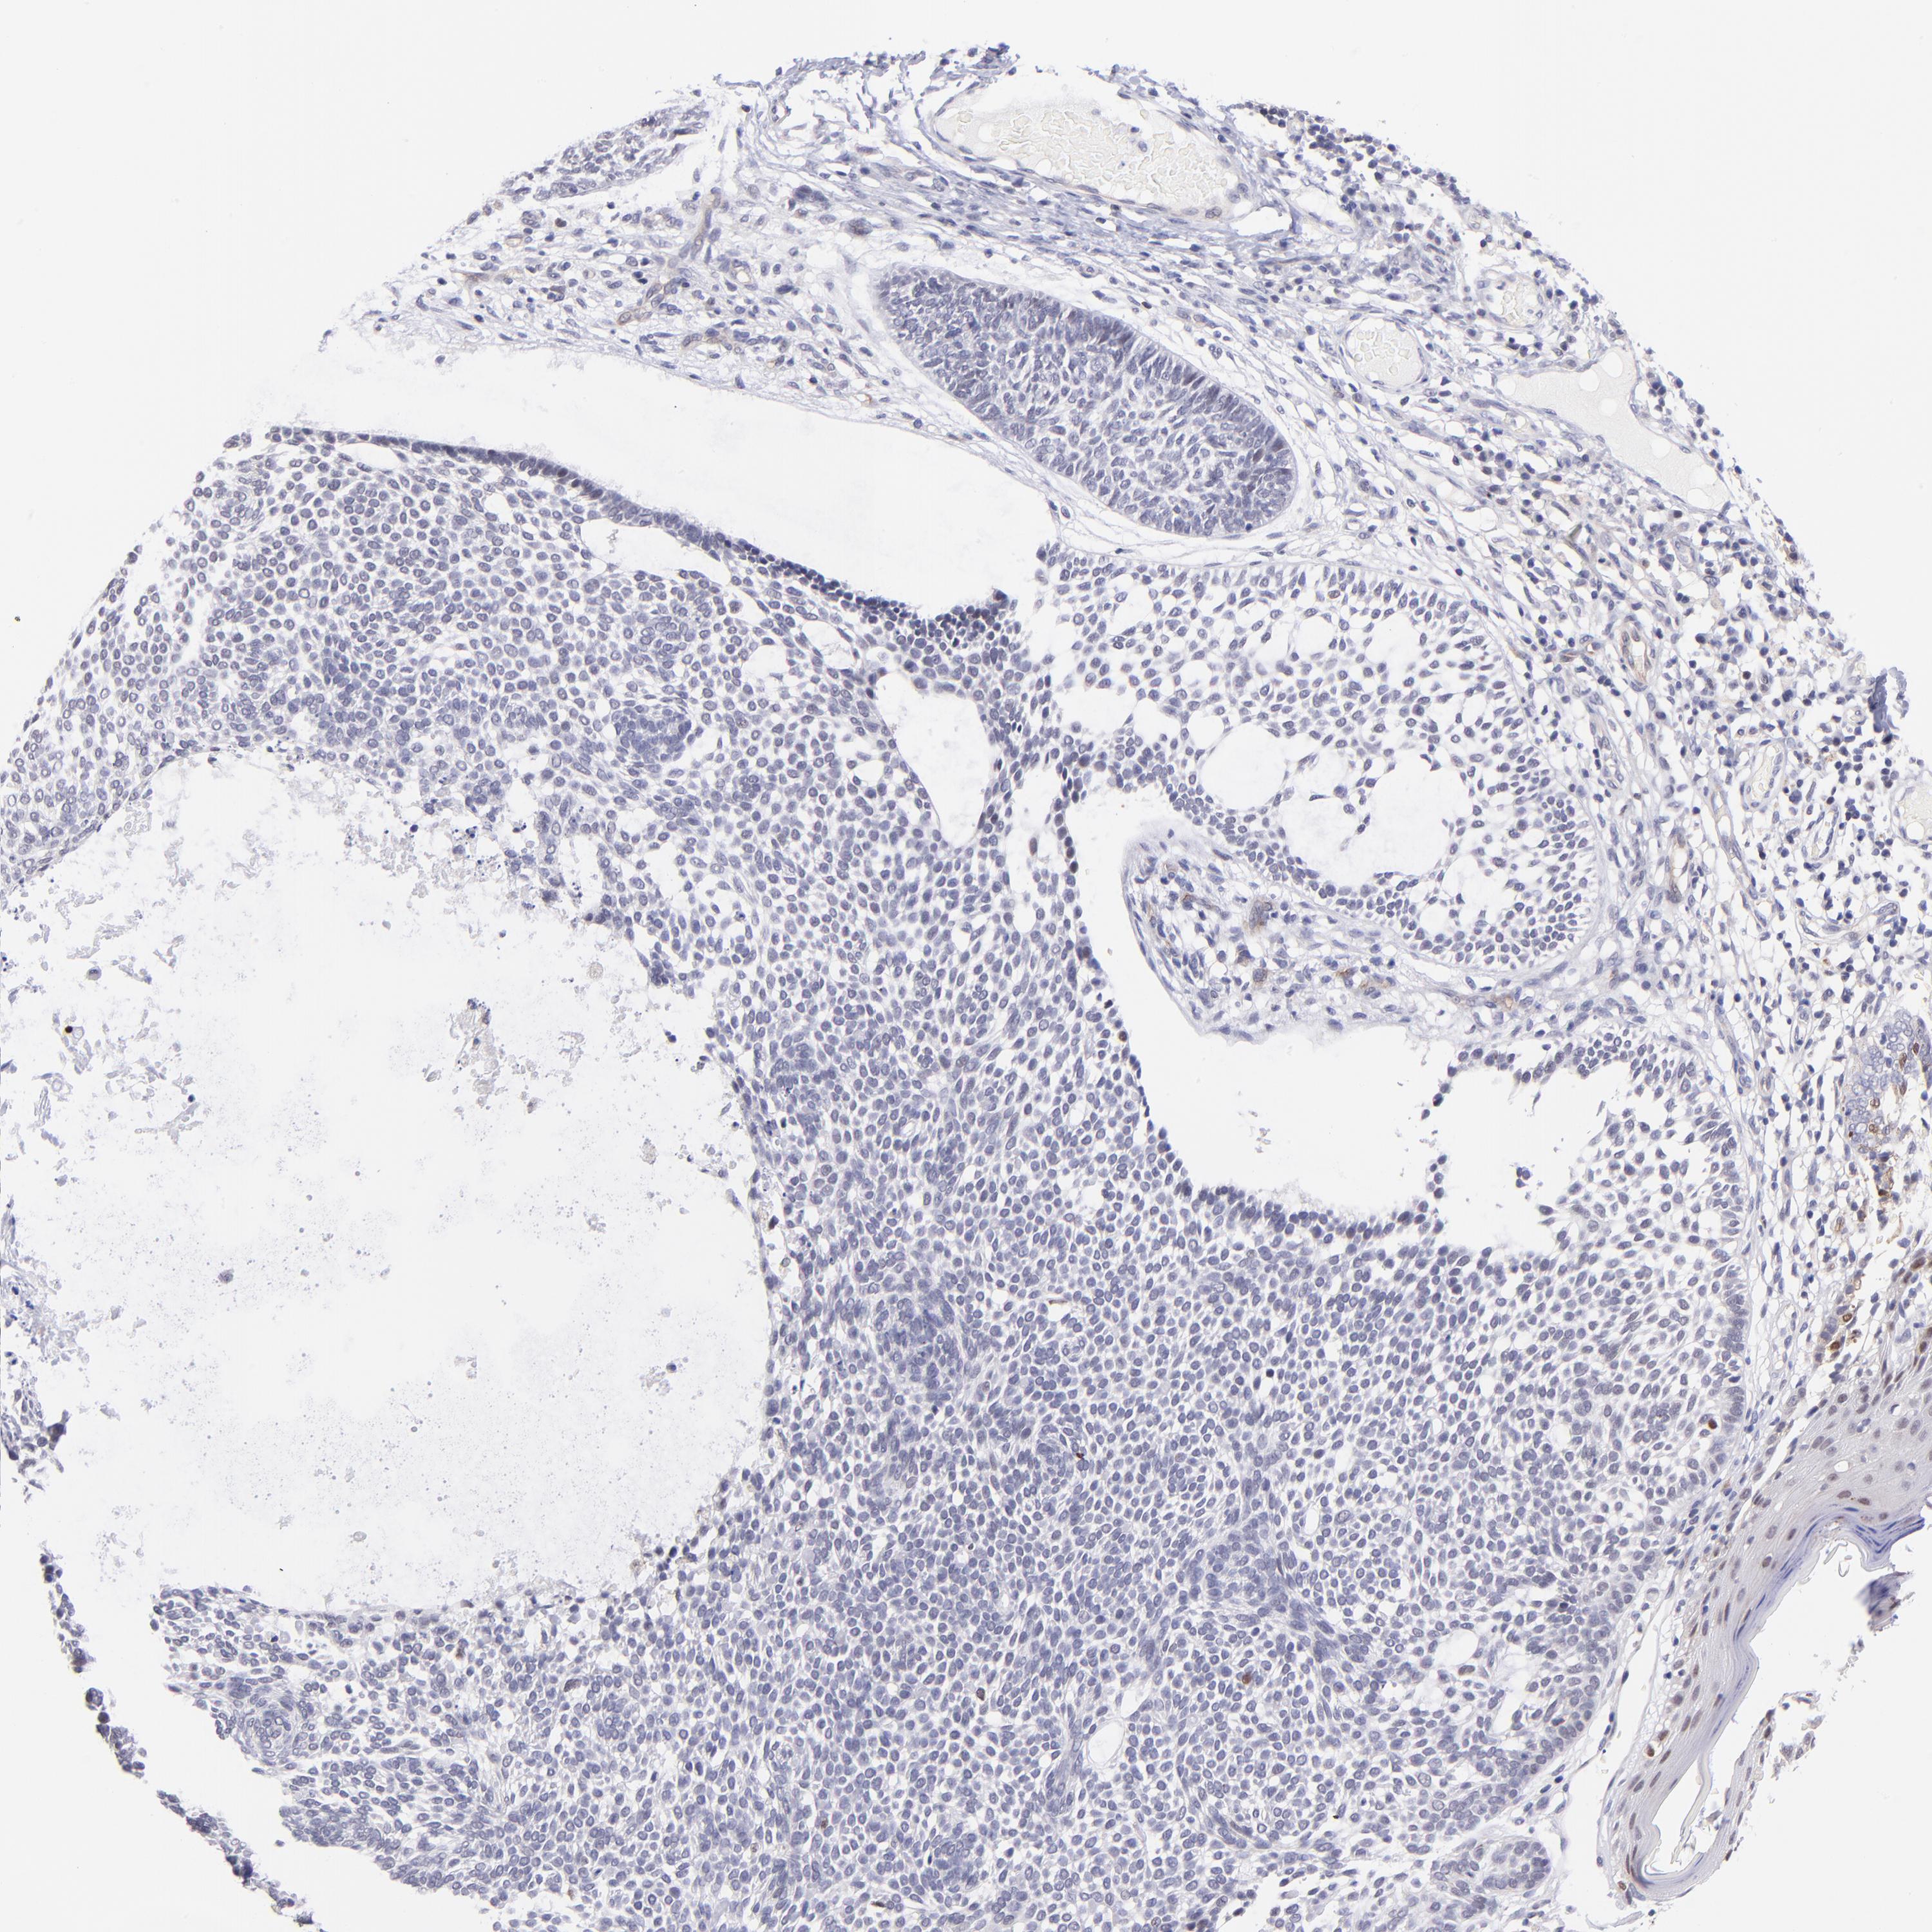

SKIN CANCER - Protein expressioni

A mouse-over function shows sample information and annotation data. Click on an image to view it in a full screen mode. Samples can be filtered based on level of antibody staining by selecting one or several of the following categories: high, medium, low and not detected. The assay and annotation is described here.

Antibody stainingi

Antibody staining in the annotated cell types in the current human tissue is reported as not detected, low, medium, or high, based on conventional immunohistochemistry profiling in selected tissues. This score is based on the combination of the staining intensity and fraction of stained cells.

Each image is clickable and will lead to virtual microscopy that enables deeper exploration of all samples and also displays staining intensity scores, fraction scores and subcellular localization as well as patient and tissue information for each sample.

Antibody HPA001923

Antibody HPA003908

Squamous cell carcinoma, NOS

Basal cell carcinoma